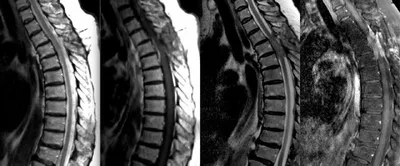

Рецидив атипичной спинальной менингиомы (первые снимки -2,5 года назад, после операции), за последний месяц - ухудшение состояния в виде нижнего парапареза и болей в спине. опухоль диффузная и муфтооб